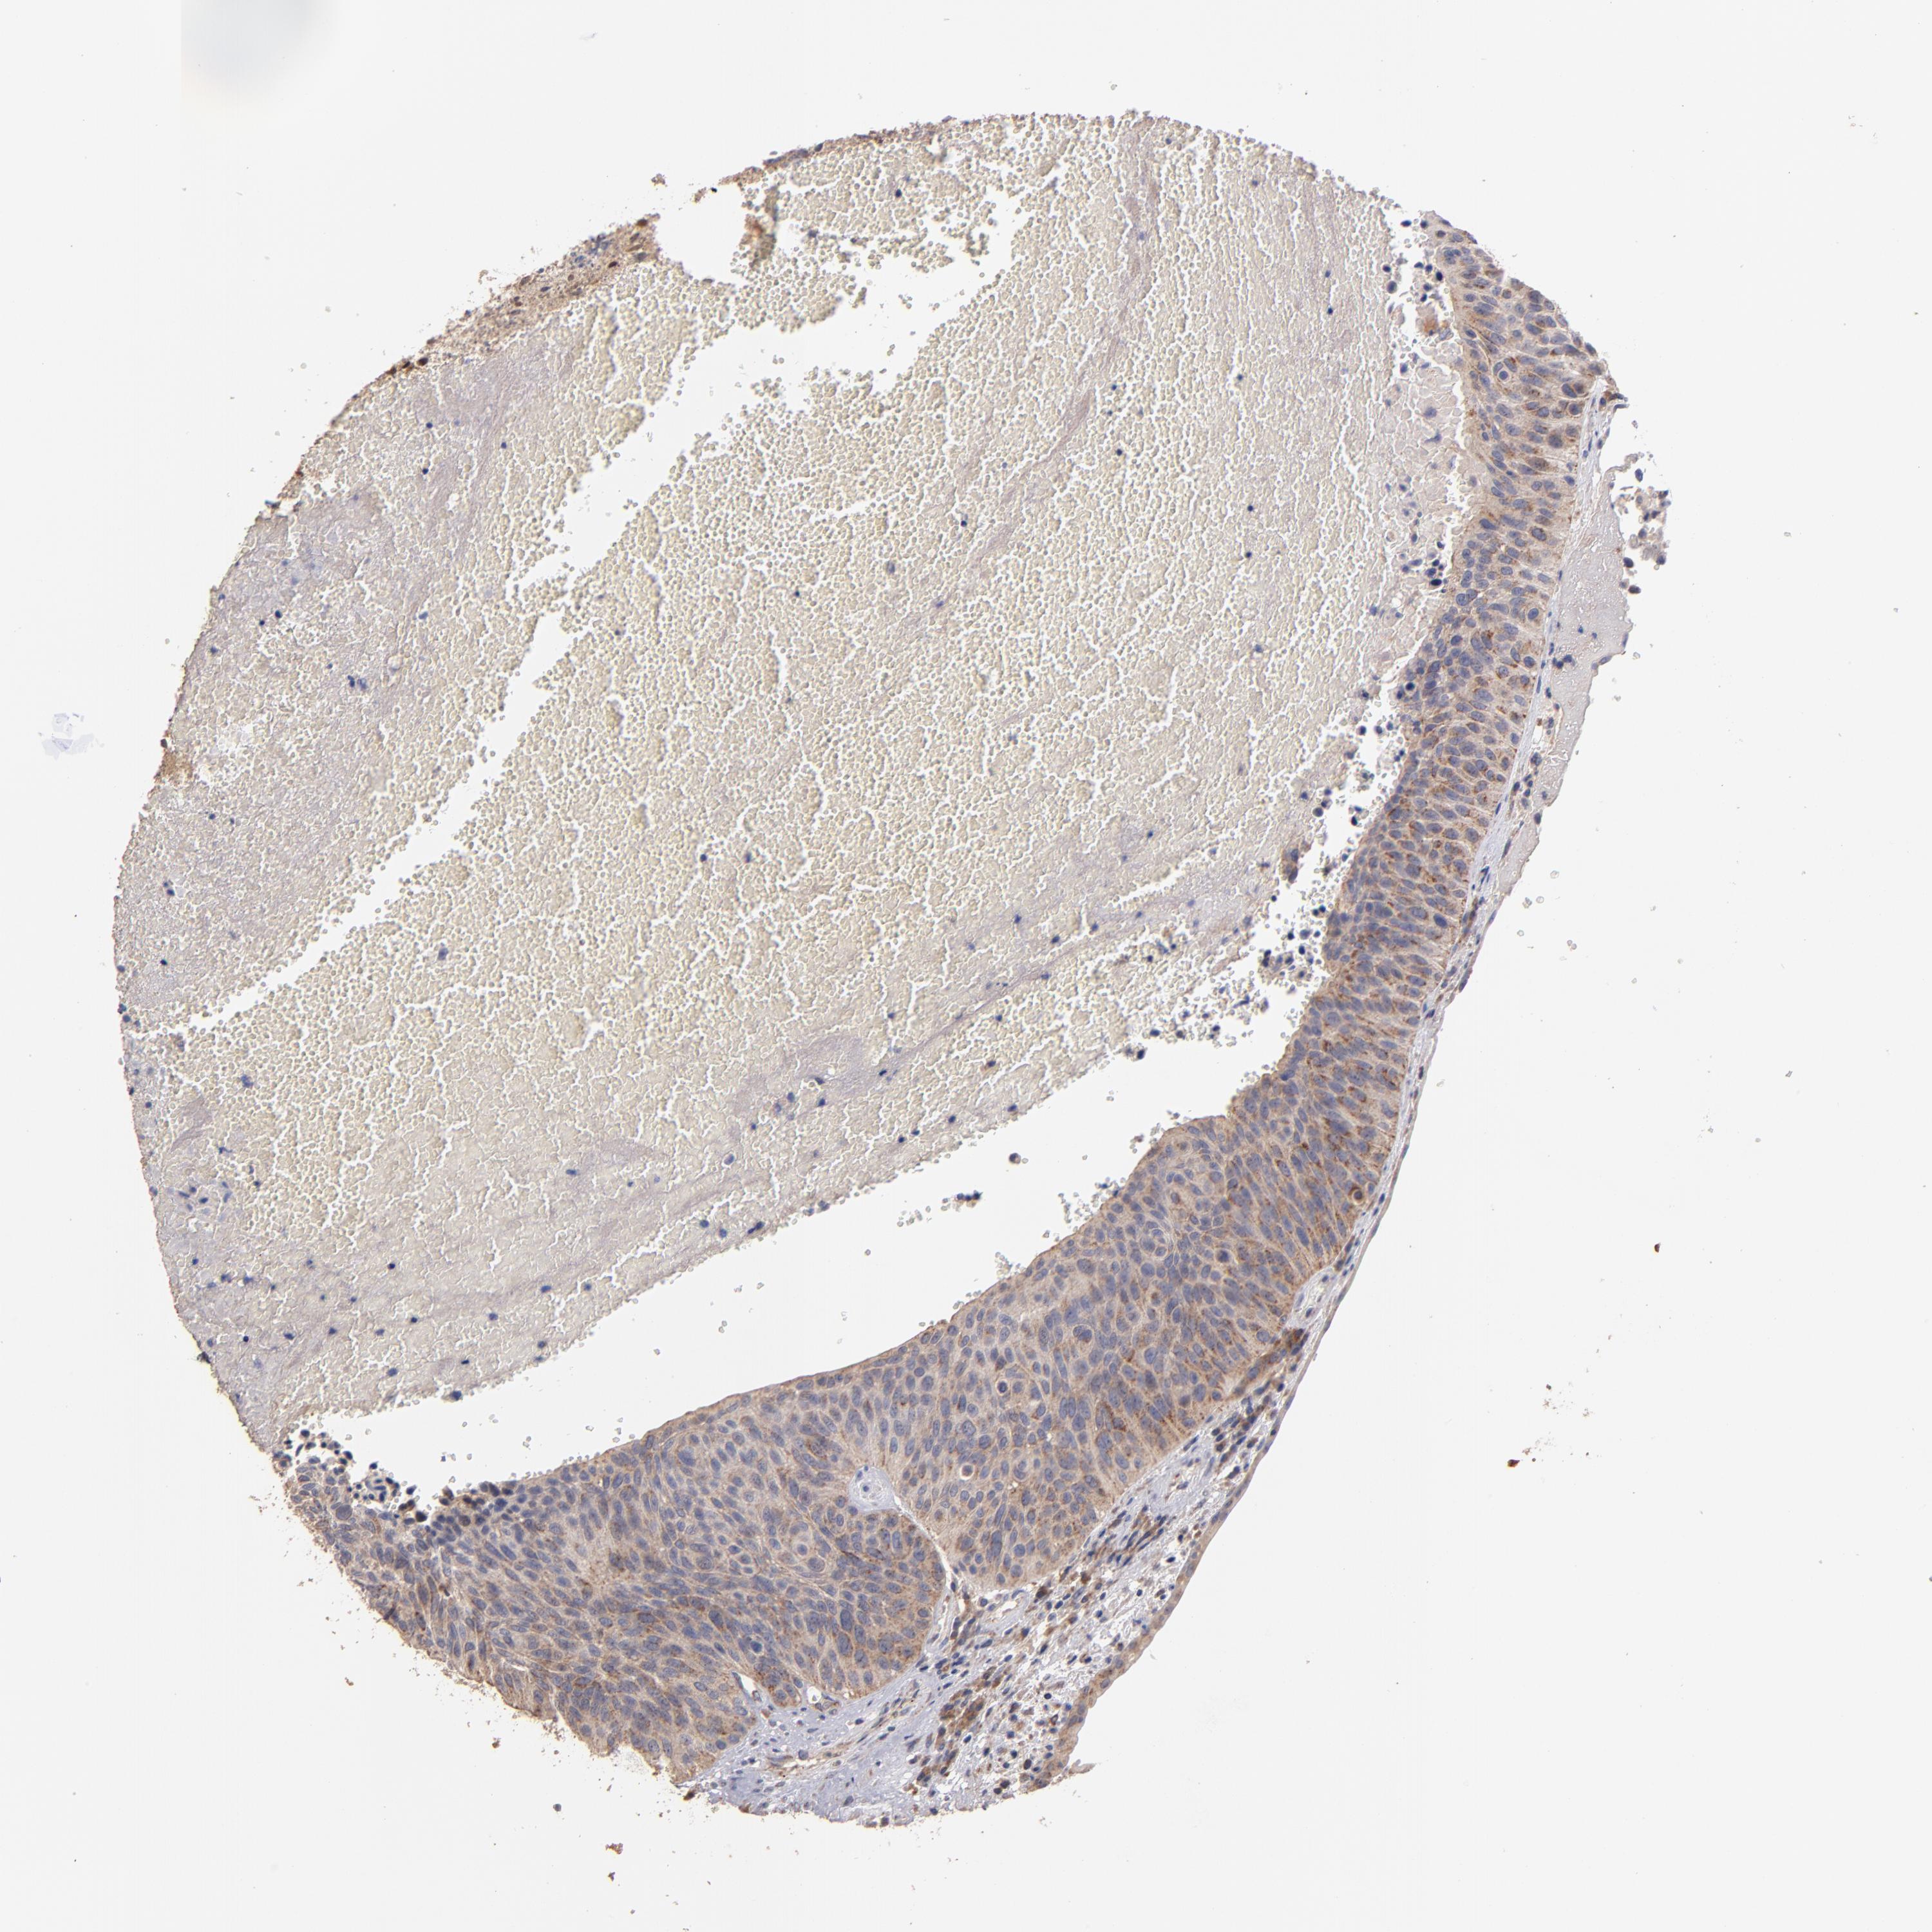

UROTHELIAL CANCER - Protein expressioni

A mouse-over function shows sample information and annotation data. Click on an image to view it in a full screen mode. Samples can be filtered based on level of antibody staining by selecting one or several of the following categories: high, medium, low and not detected. The assay and annotation is described here.

Note that samples used for immunohistochemistry by the Human Protein Atlas do not correspond to samples in the TCGA dataset.

Antibody stainingi

Antibody staining in the annotated cell types in the current human tissue is reported as not detected, low, medium, or high, based on conventional immunohistochemistry profiling in selected tissues. This score is based on the combination of the staining intensity and fraction of stained cells.

Each image is clickable and will lead to virtual microscopy that enables deeper exploration of all samples and also displays staining intensity scores, fraction scores and subcellular localization as well as patient and tissue information for each sample.

Antibody HPA001825

Antibody CAB003857

Urothelial carcinoma, High grade

Urothelial carcinoma, Low grade